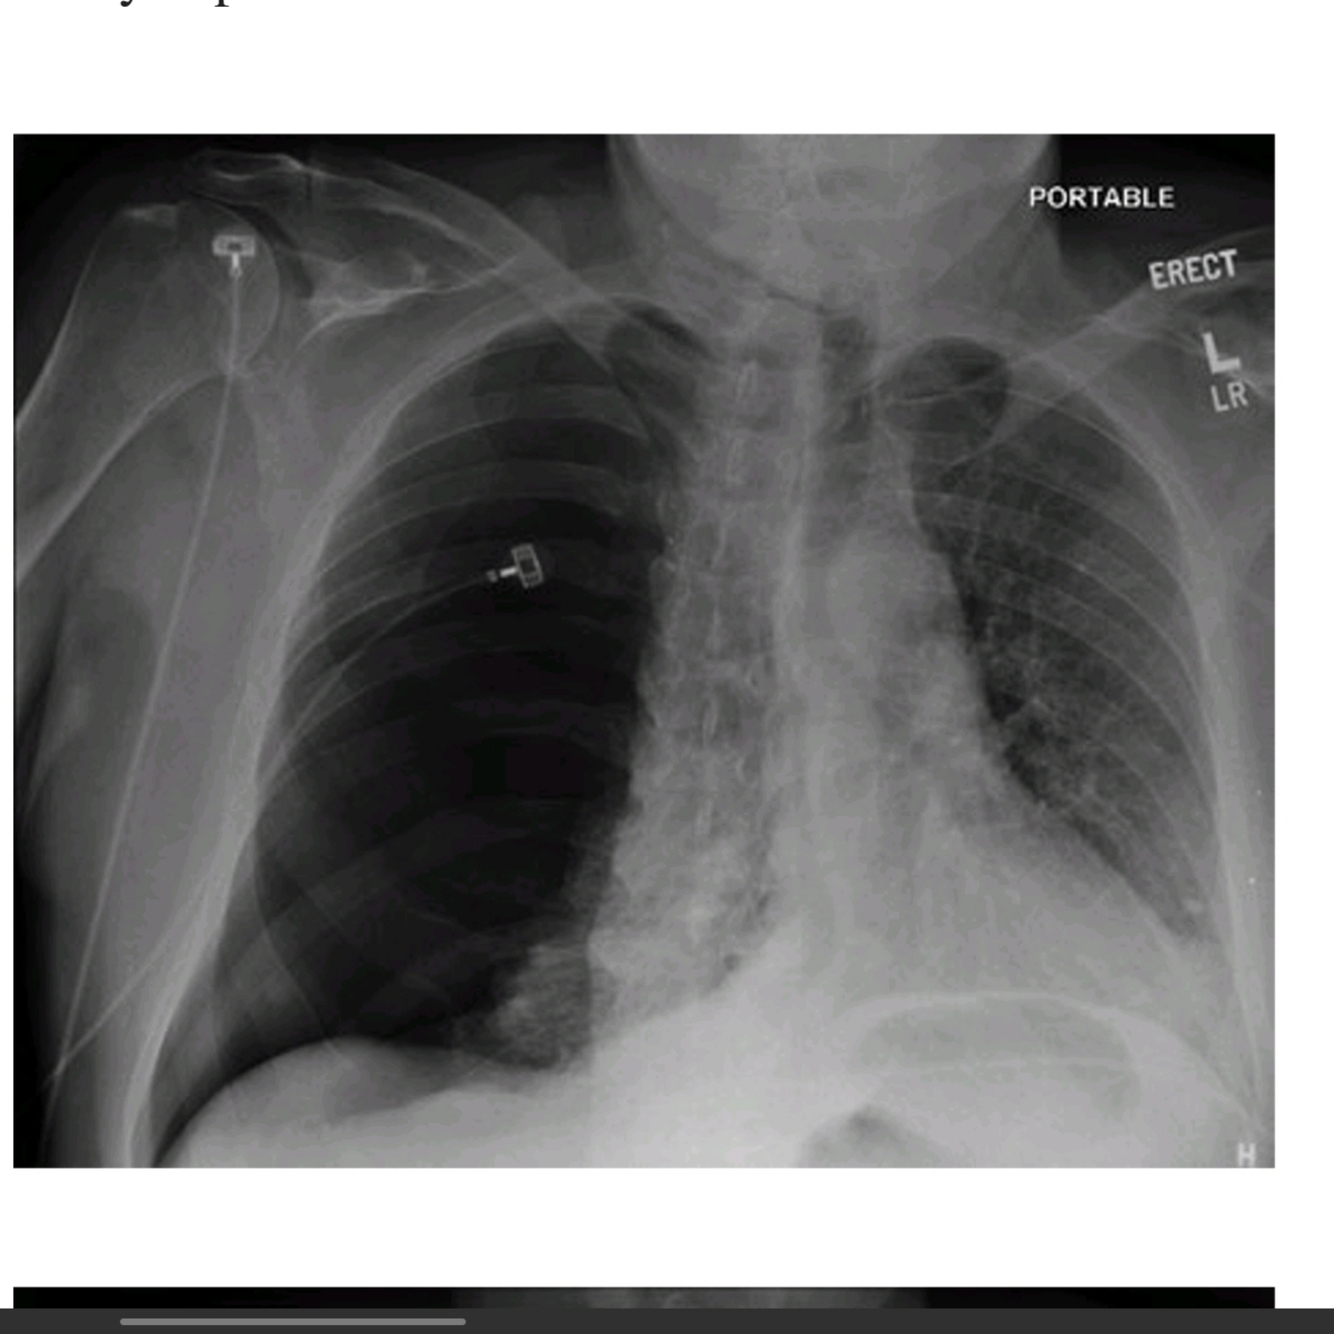

A 67 year old man is scheduled for repair of his inguinal hernia. On closer questioning he reviled history of haemoptysis,. Hi P CXR is shown.

1. Describe the xray

2. What is the underlying diagnosis

A

Diagnosis: COPD

Features:

° Hyperinflation a flat diaphragms , there should be 7 intercostals spaces seen

° Horizontal orientation of ribs

° osteopenic ribs 2° chronic steroid use